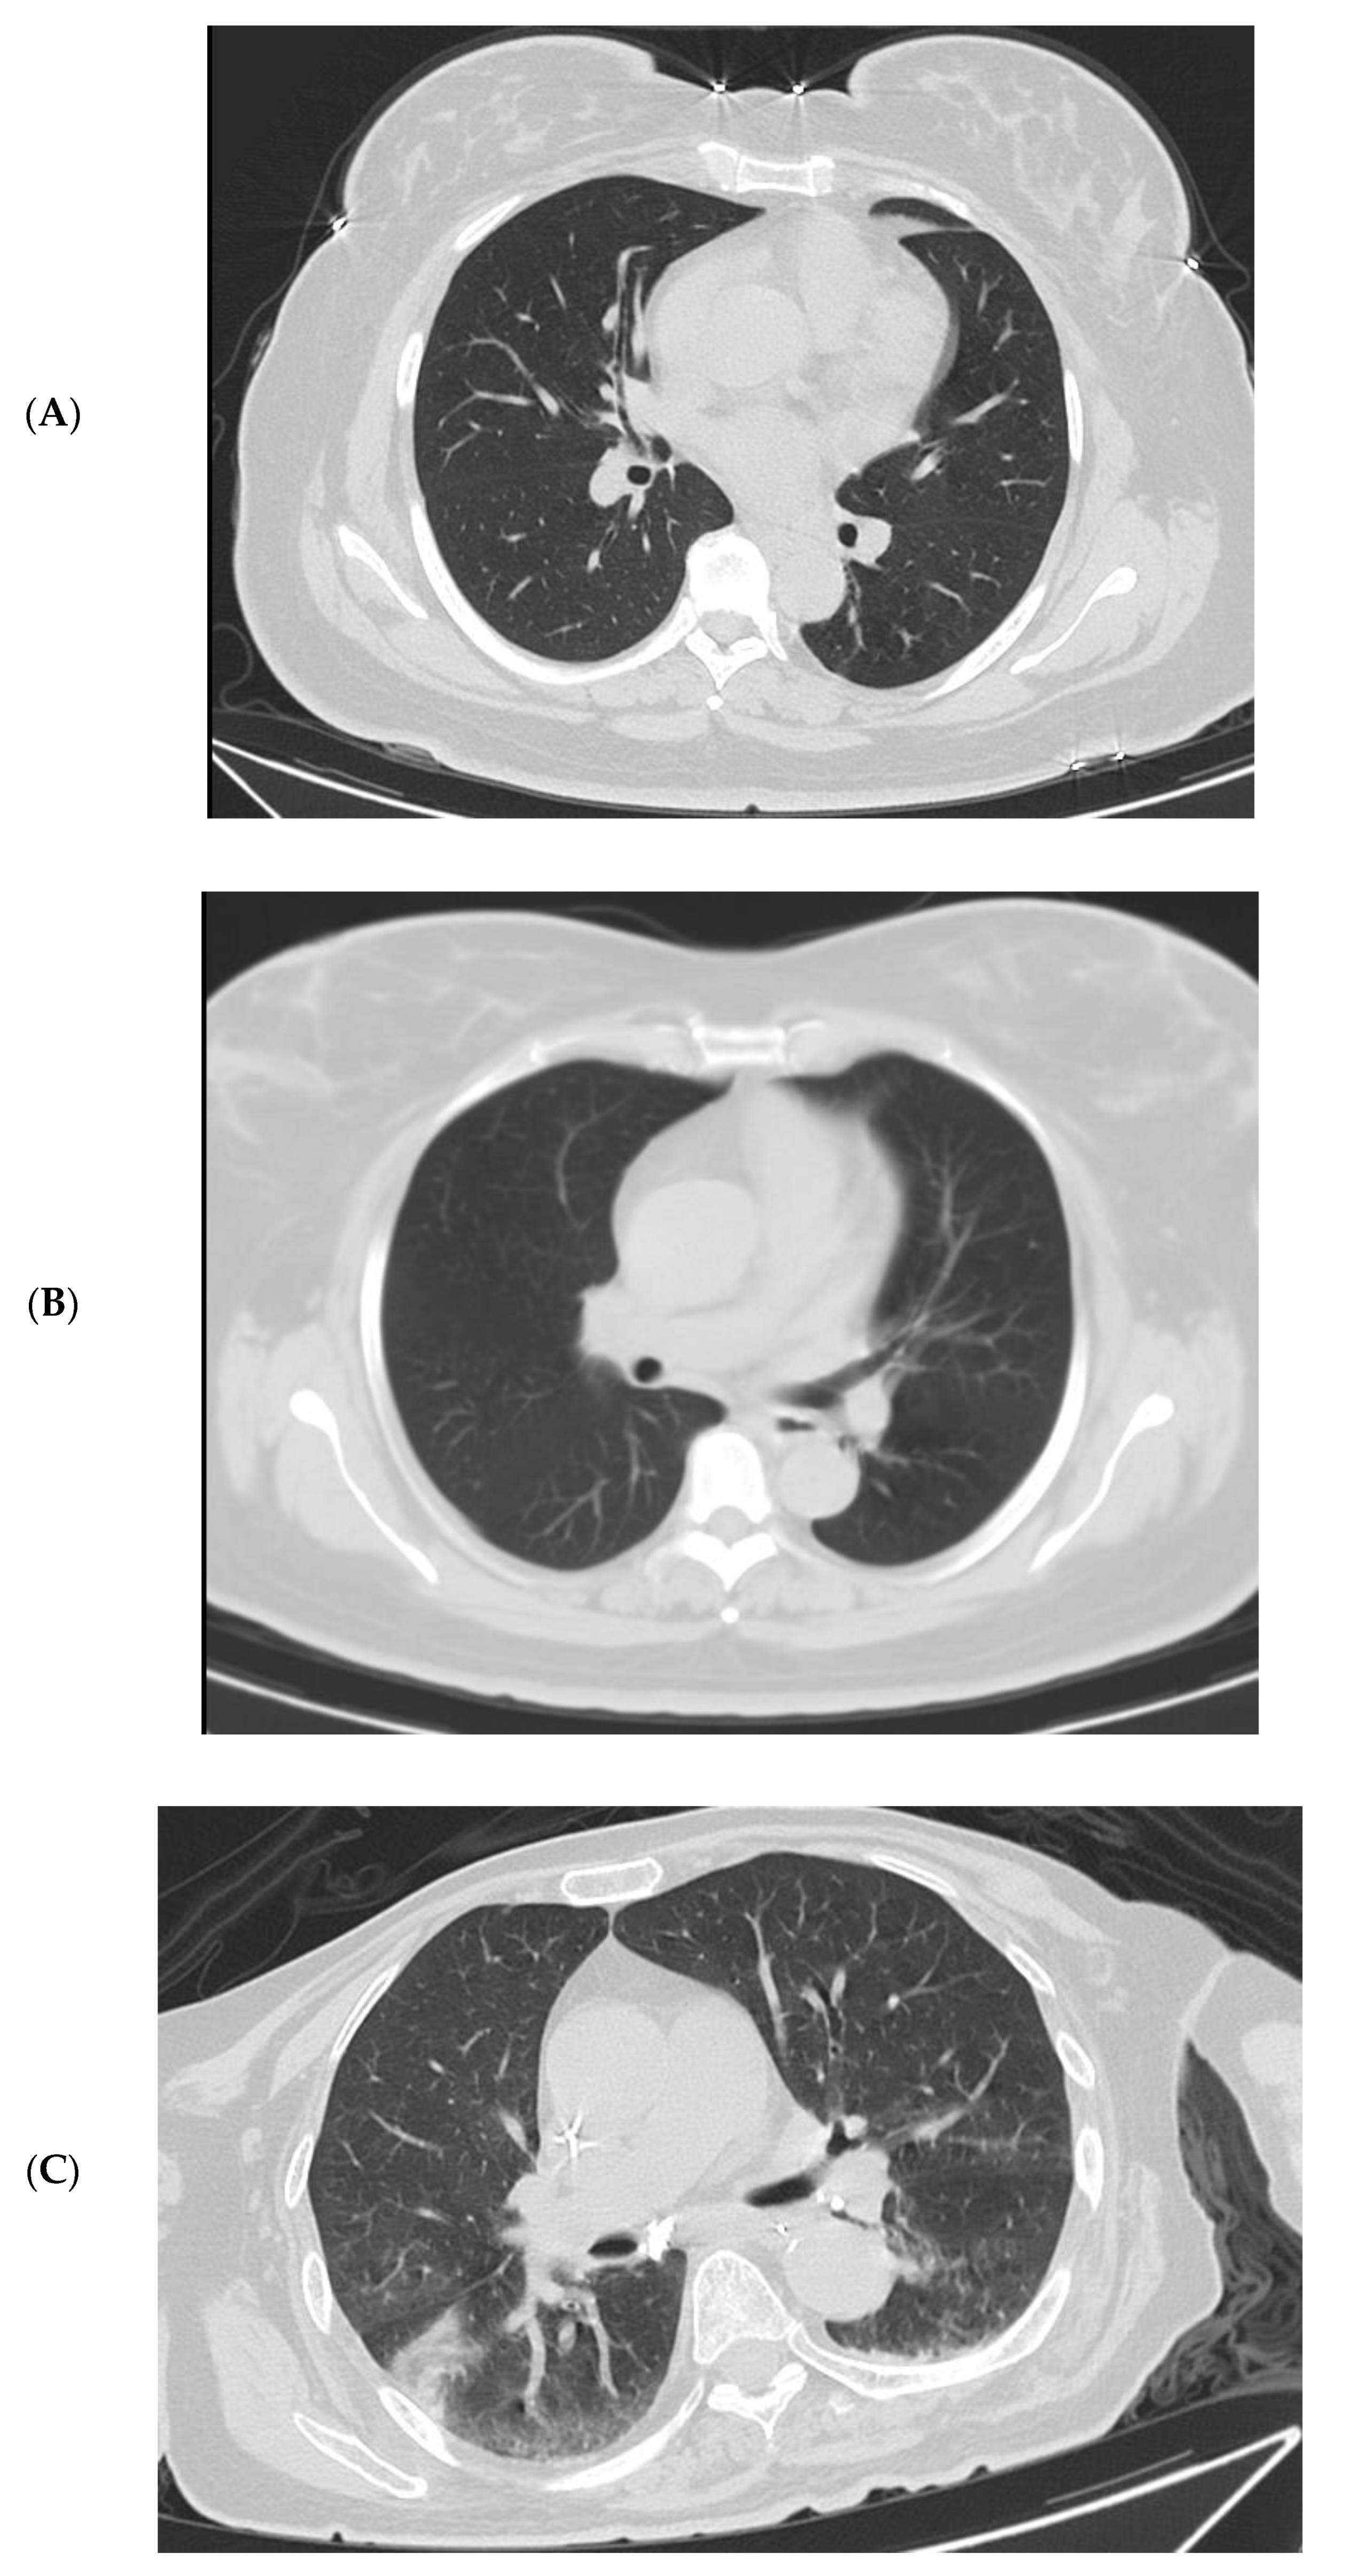

3.4. Imaging Changes in Disease Progression